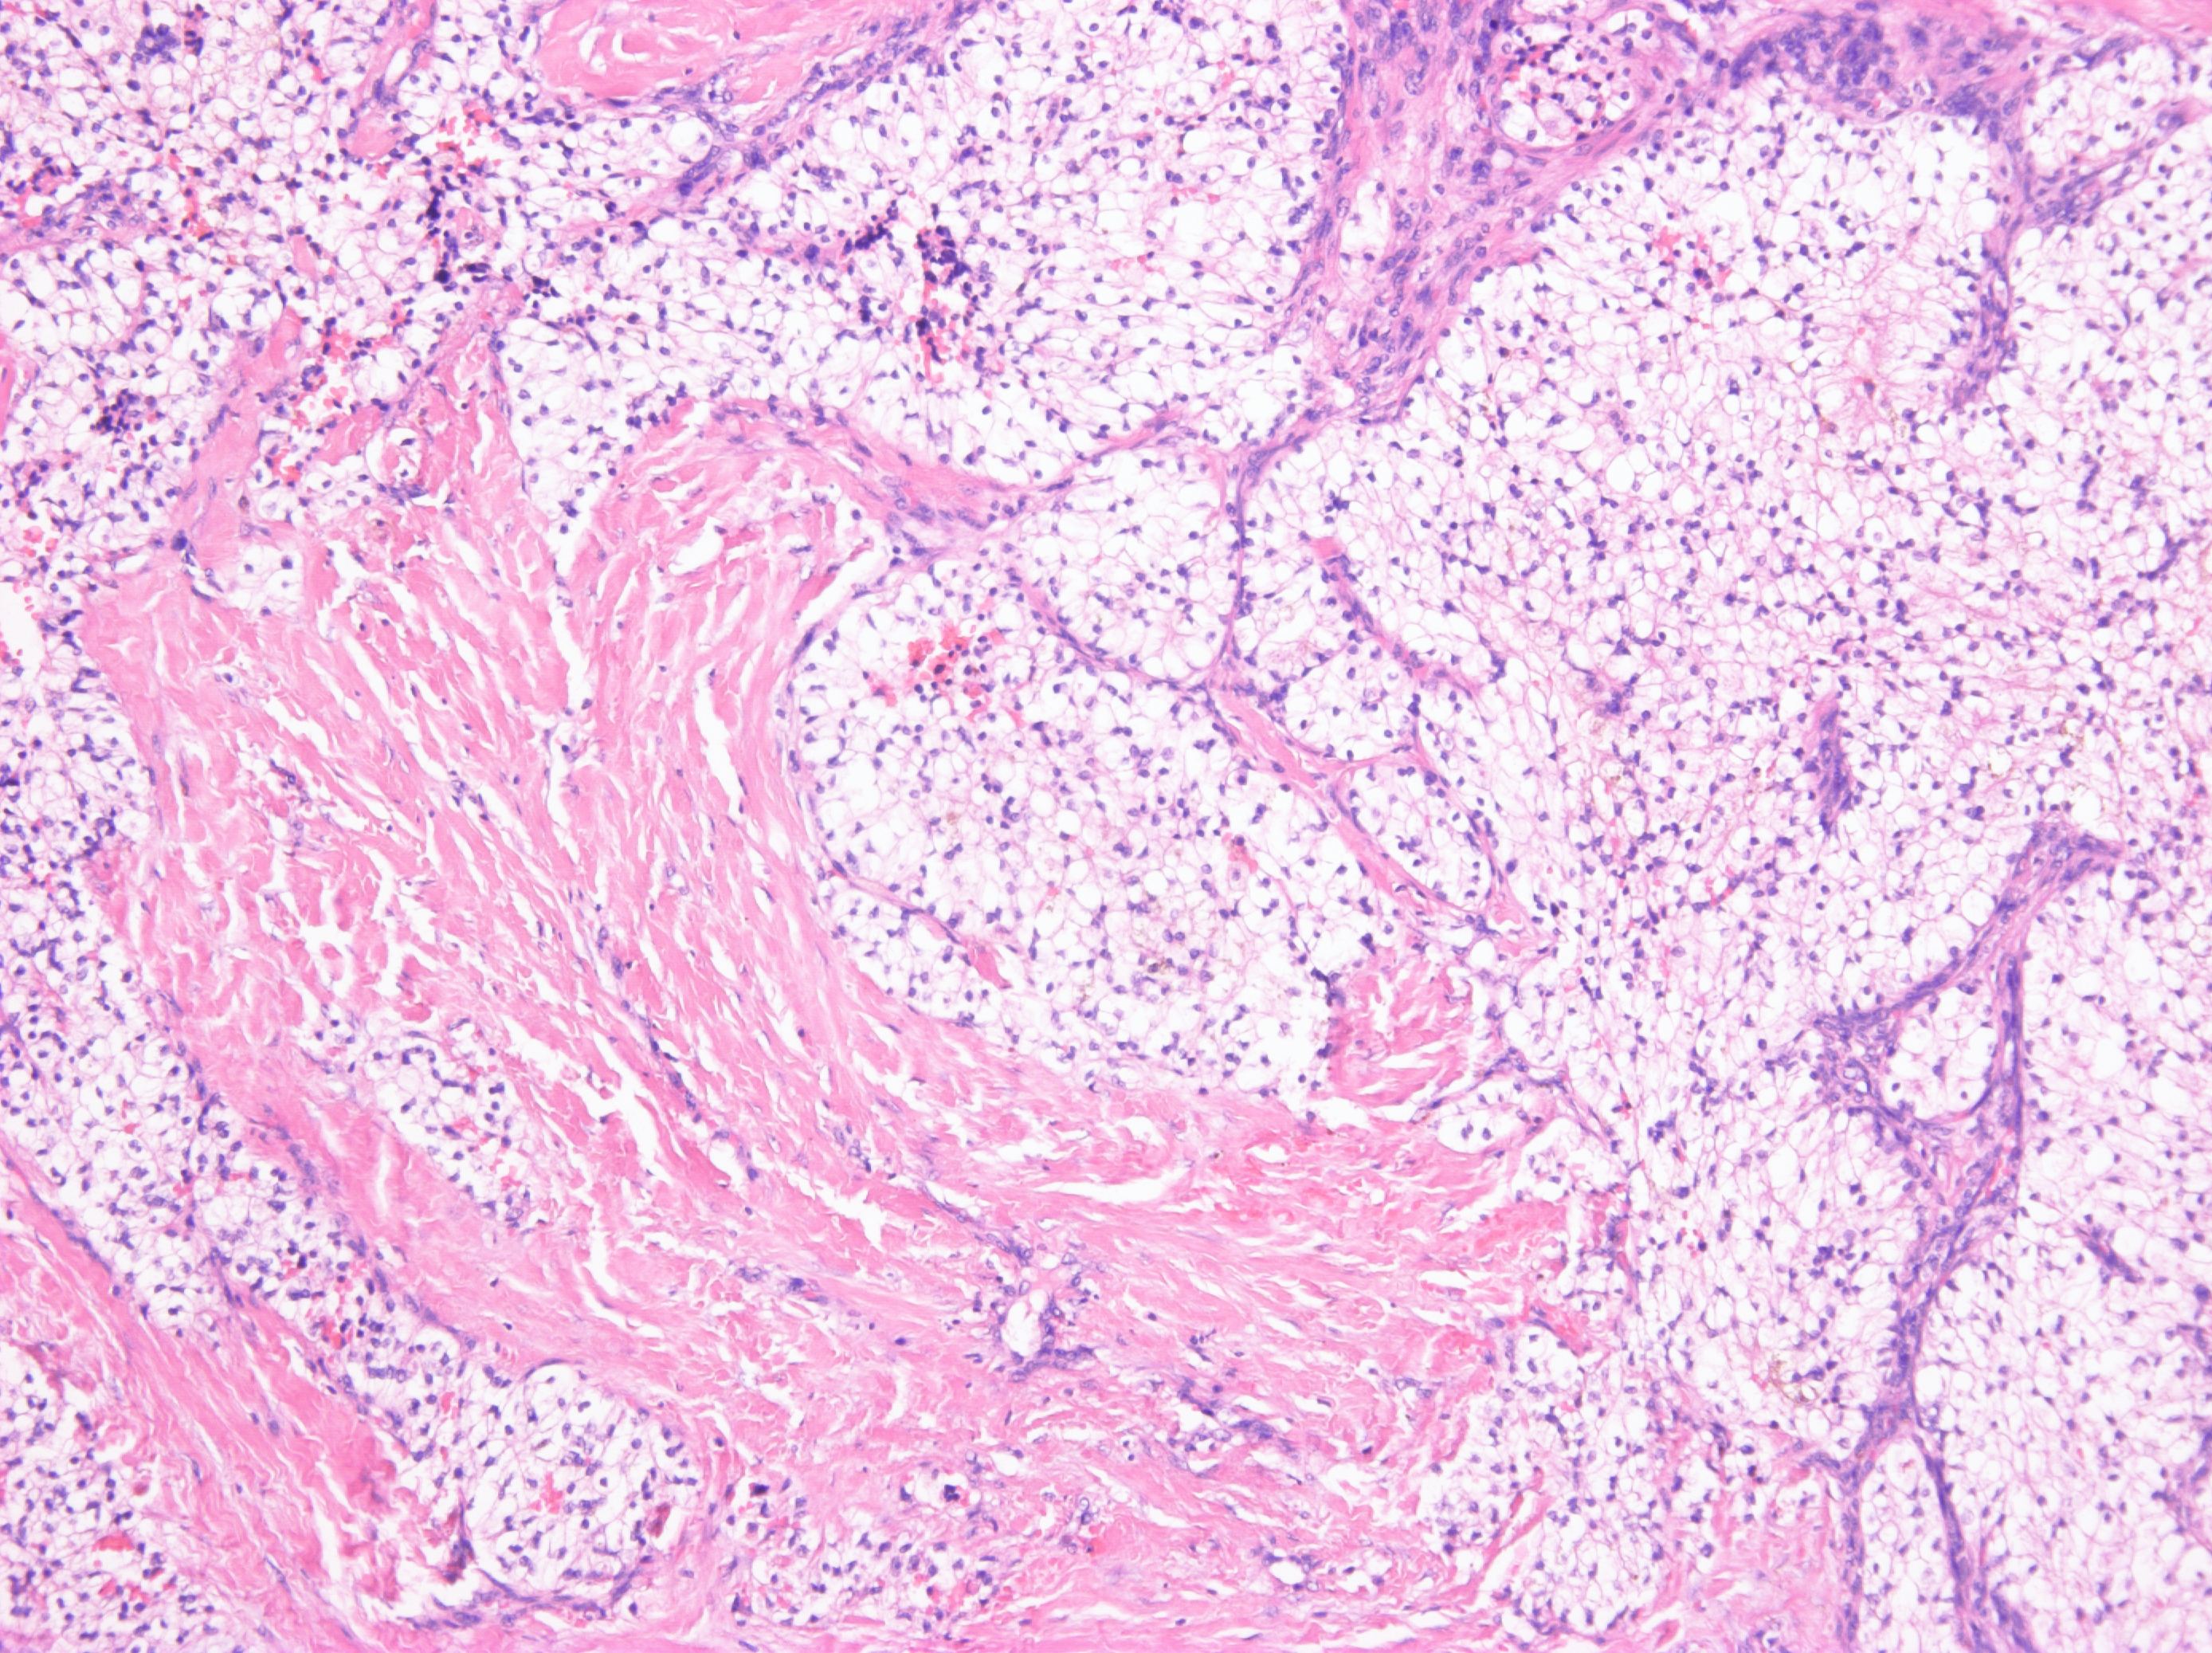

Consensus grade: Renal cell carcinoma with leiomyomatous stroma

Since there is a lot of pink stroma, this is probably thought to be clear cell renal cell carcinoma with leiomyomatous stroma but the photos show a stroma which looks fibrous to me so garden variety clear cell renal cell carcinoma is a better diagnosis for the photos. |

hard to be sure the stroma is muscle in these images |

Kidney tumor, male 62-year-old. Tumor well circumscribed, yellow color with gray strands on gross section. Tumor composed of clear cell elements resembling cells of typical clear cell RCC. Fibroleiomyomatous stroma was prominent. No sarcomatoid changes were present.

Dg: Renal cell carcinoma with (fibro)leiomyomatous stroma